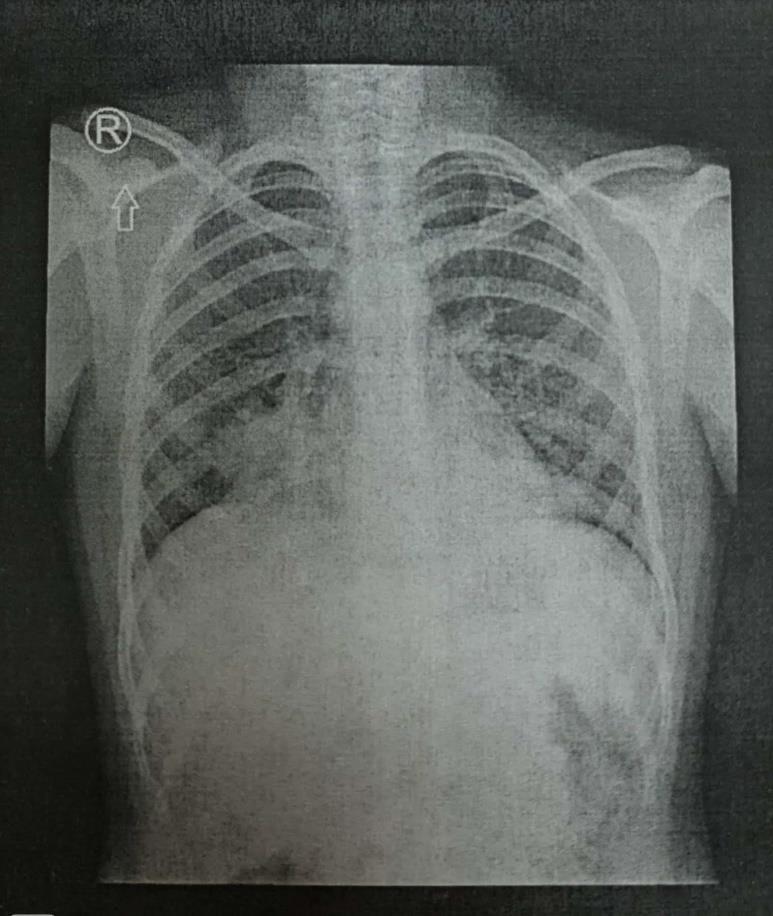

Pytanie 119

U dziecka z długo utrzymującymi się płucnymi zmianami zapalnymi uwidocznionymi jak w załączonym radiogramie klatki piersiowej podjęto decyzję wykonania badania bronchofiberoskopowego. Najkorzystniejszym miejscem zaklinowania bronchoskopu dla wykonania BAL-u z następową oceną bakteriologiczną uzyskanego płynu będą oskrzela segmentowe po stronie prawej o numerach: